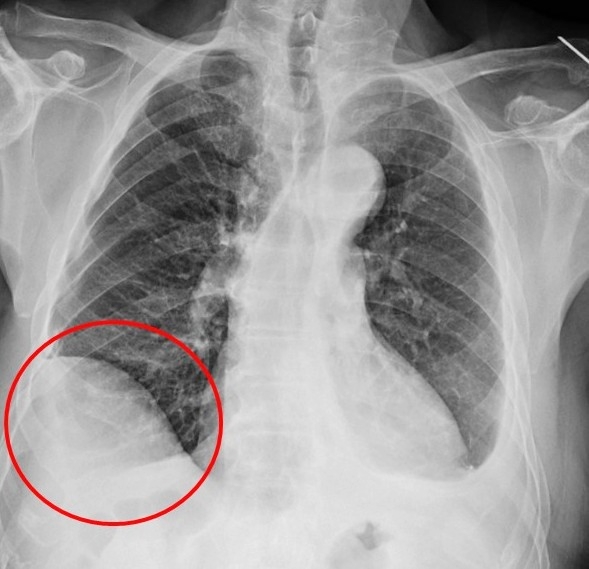

▲病人創傷後橫膈膜沾黏,右側橫膈膜明顯升高。(圖╱仁愛長庚醫院提供)

廖啟耀主任指出,仁愛與長庚醫療體系聯盟醫院近年來積極引進達文西機器人手術系統,並成立微創暨達文西手術中心,致力推動高品質、低侵襲性的手術照護。手術中病人的橫隔膜如果符合預期和肺臟沾黏,因此手術空間也較為狹小,達文西機器人手術可提供穩定的操作及清晰的手術視野,這對於外科醫師在分沾黏上是如虎添翼。達文西手術在這方面優勢更顯得突出,透過穩定且精細的操作,團隊將吳先生的橫隔膜與肺臟分離,並完成之後的肺節切除手術。